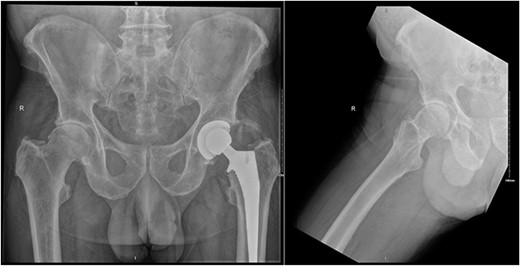

Subsequently, this patient’s case was discussed at our PJI multidisciplinary meeting among the infectious diseases, microbiology, and orthopaedic teams. A consensus decision was made to treat the patient with a 12-week course of IV Vancomycin given the clinical presentation, radiological, and intraoperative findings. After completing his 12 weeks of IV antibiotics, his inflammatory markers returned to normal limits (Fig. 5). At 6-month follow-up, our patient was mobilizing independently without any signs of infection recurrence. His radiographs showed the implant was in a satisfactory position with no evidence of loosening (Fig. 6).

AP pelvis and lateral right hip radiographs at 6 months post debridement, antibiotics, implant retention (DAIR) procedure.